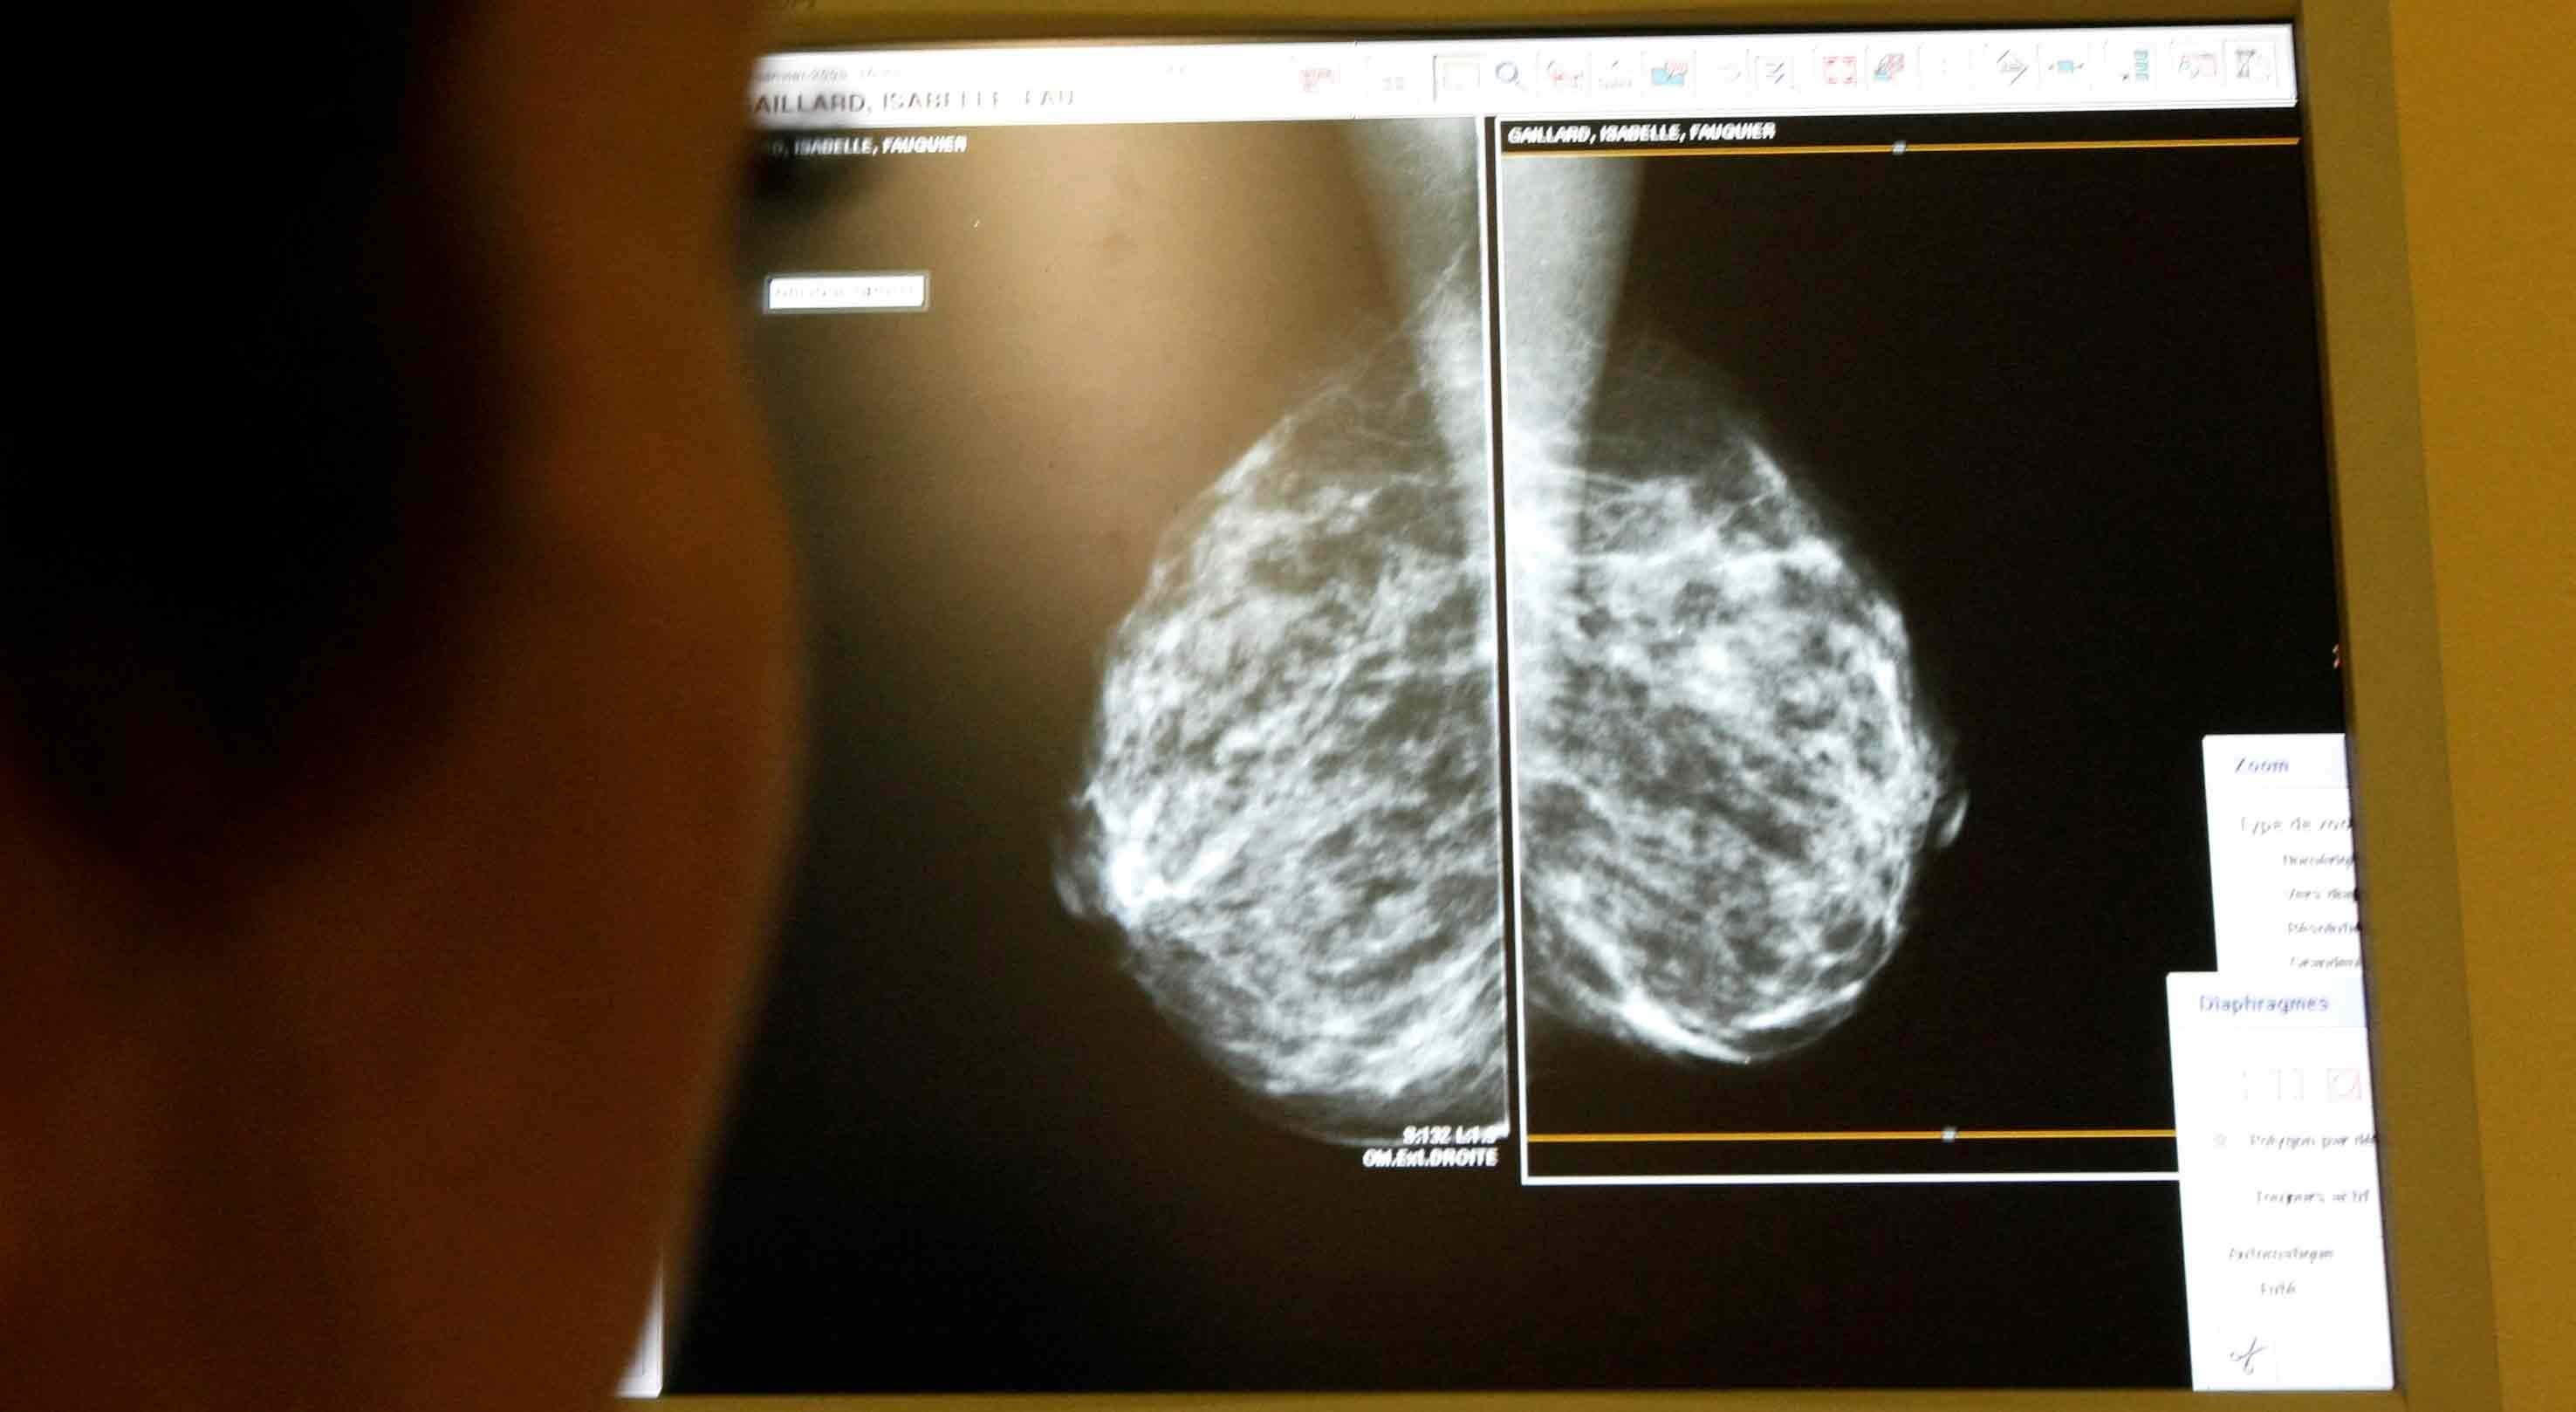

Onze tipos de cancro aumentam entre os jovens no Reino Unido e os cientistas já têm primeira pista sobre a razão

As razões para o aumento dos casos de cancro em pessoas no final da adolescência e nas casas dos 20, 30 e 40 anos intrigam os cientistas há vários anos. As razões para o aumento dos casos de cancro em pessoas no final da adolescência e nas casas dos 20, 30 e 40 anos intrigam os cientistas há vários anos.